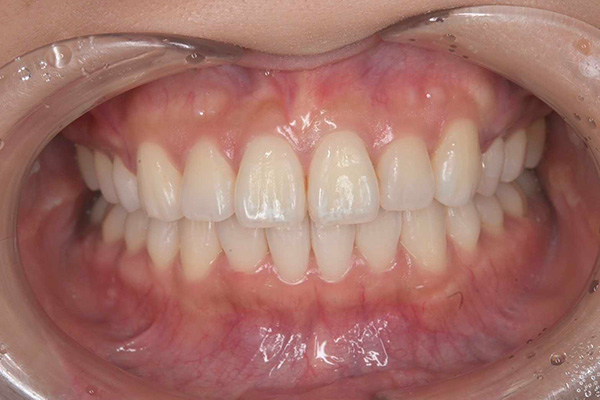

⑦ インプラント治療とセラミック治療

治療中

治療後

年代・性別

40代女性

セカンドオピニオン

治療内容

インプラント治療

セラミック治療

治療期間・回数

6ヶ月

費用

約80万円

リスク・副作用

インプラント手術には合併症が起きる場合があります。

修復物は破損することもございます。

治療により痛みが出ることもございます。